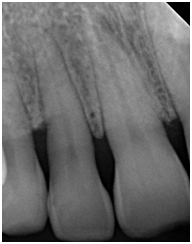

A 42- year-old white female with a non-contributory medical history was referred in May 2014 for a periodontal examination and treatment and specifically for a localized increasing pocket depth on maxillary right lateral incisor which had an initial PD of 9 mm on the disto-palatal aspect and Miller Class I mobility with BOP (Table 1). Bone loss, as determined by the radiograph (Figure 1) was an angular defect. The patient’s oral hygiene and plaque control were very good.

Figure 1 Pretreatment radiograph of tooth #7 with angular bony defect on the distal aspect.